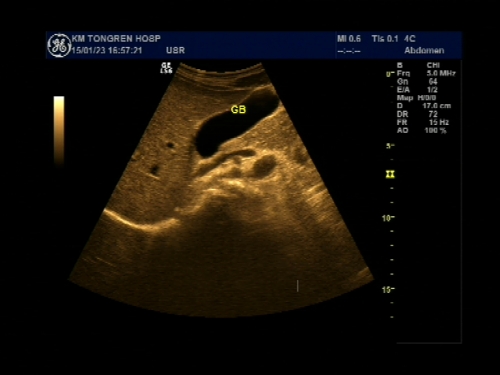

超声声像图能显示肝脏切面形态、大小、肝内实质结构、管道系统及肝周邻,并能根据肝内管道系统区分肝脏各叶、各段,对病变进行定位诊断。彩色多普勒超声能显示肝脏的血流,并能对肝脏的血流动力学参数进行测定,不仅能诊断肝脏的血管病变,还能了解正常肝脏及病变肝脏的血供及回流状态,目前已成为临床诊断肝脏疾病的常规检查方法。

右肋间斜断扫查

肝缘下斜断扫查